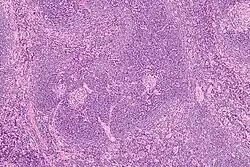

![]() Histology of a normal secondary lymphoid follicle, with yellow arrows pointing at the mantle zone. | |

The mantle zone (or just mantle) of a lymphatic nodule (or lymphatic follicle) is an outer ring of small lymphocytes surrounding a germinal center.[1]

It is also known as the "corona".[2]

It contains transient lymphocytes.[3]

It is the location of the lymphoma in mantle cell lymphoma.

Mantle zone expansion may be seen in benign, such as Castleman disease, and malignancy, i.e., Mantle cell lymphoma. Tcl-1 is expressed in the mantle zone.